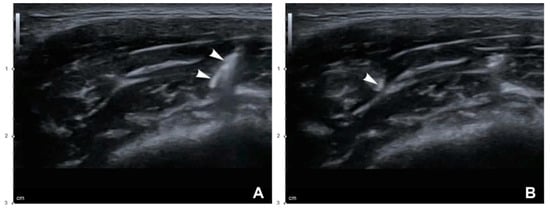

Figure 6.

US-guided dual-plane BoNT-A injections into the masseter. White arrowheads indicate a needle tip: (A) deep injection (B mode, transverse view, 15-MHz linear transducer) and (B) superficial injection (B mode, transverse view, 15-MHz linear transducer).